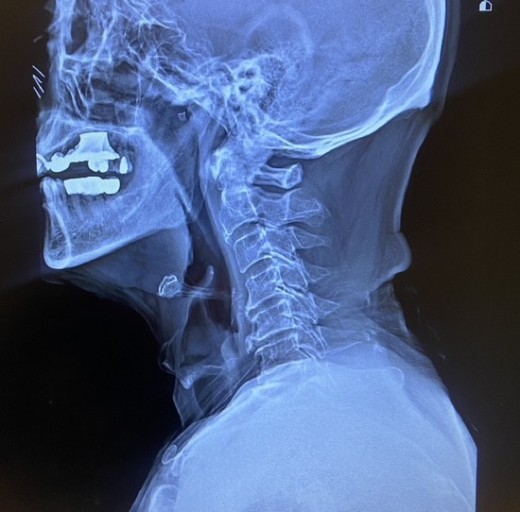

목디스크(경추 추간판 탈출증)는 경추(목뼈) 사이의 디스크가 탈출하거나 변형되어 신경을 압박하는 질환입니다. 이로 인해 다양한 증상이 나타날 수 있으며, 아래에 10가지를 아주 자세히 설명드립니다.

8. 목 움직임 제한

- 목을 돌리거나 숙이는 등의 움직임이 어려워지고, 특정 방향으로 움직일 때 통증이 심해질 수 있습니다.

- 심한 경우, 목을 자유롭게 움직이지 못하고 고정된 자세를 유지하게 됩니다.